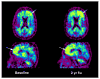

Imaging agents capable of assessing amyloid-beta (Abeta) content in vivo in the brains of Alzheimer's disease (AD) subjects likely will be important as diagnostic agents to detect Abeta plaques in the brain as well as to help test the amyloid cascade hypothesis of AD and as an aid to assess the efficacy of anti-amyloid therapeutics currently under development and in clinical trials. Positron emission tomography (PET) imaging studies of amyloid deposition in human subjects with several Abeta imaging agents are currently underway. We reported the first PET studies of the carbon 11-labeled thioflavin-T derivative Pittsburgh Compound B in 2004, and this work has subsequently been extended to include a variety of subject groups, including AD patients, mild cognitive impairment patients and healthy controls. The ability to quantify regional Abeta plaque load in the brains of living human subjects has provided a means to begin to apply this technology as a diagnostic agent to detect regional concentrations of Abeta plaques and as a surrogate marker of therapeutic efficacy in anti-amyloid drug trials.